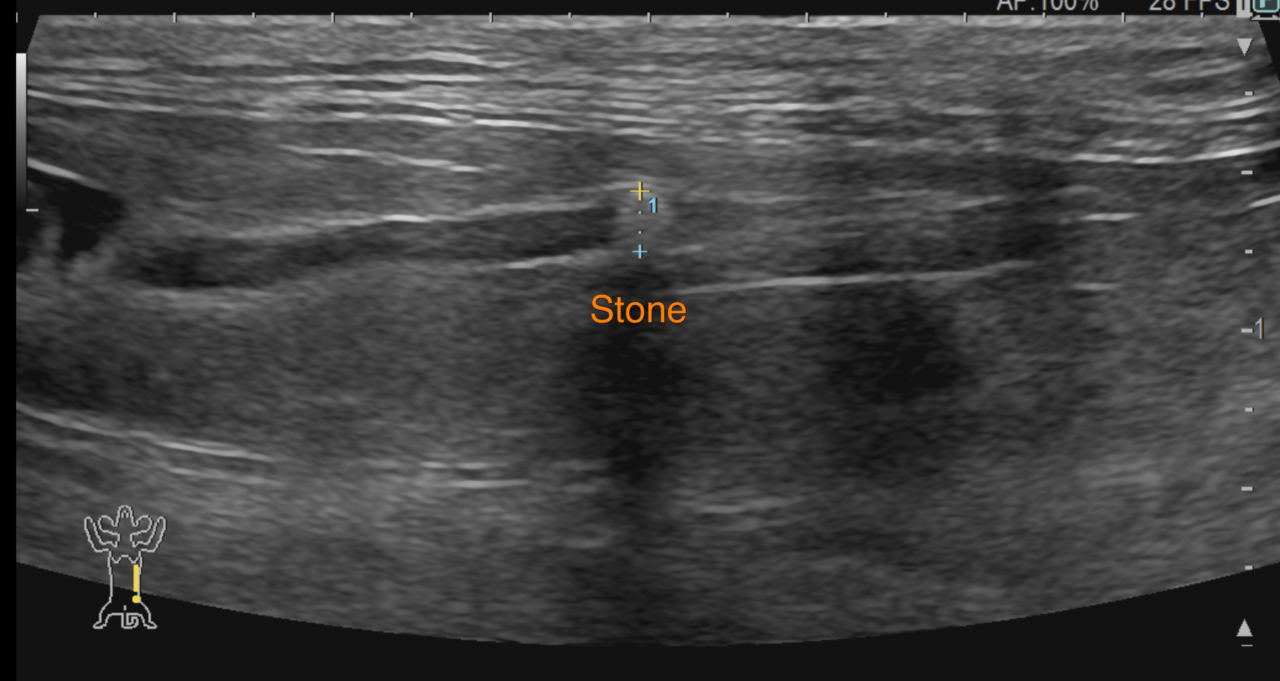

猫さんの尿管に結石がつまって腎臓の数値が上昇してきており、なんとかしてほしいと主治医から連絡がありました。マイクロサージェリーで結石を摘除し、尿管膀胱新吻合術を行いました。尿管は結石により炎症を起こしていたので術後の吻合部位に狭窄が生じることがあります。今回は短尺型尿管ステントを留置しています。これでたくさんおしっこが出るようになります。